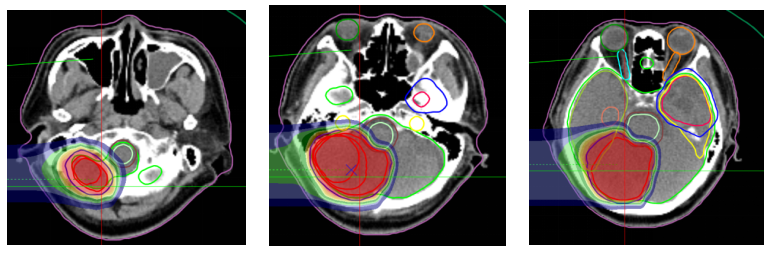

Figure 6: The prescribed dose for the left frontotemporal lobe mass is 45 Gy (RBE) in 15 fractions.

Figure 7: Treatment plan: Prescription dose: The PTVm prescription dose is 60 Gy (RBE) in 20 fractions.